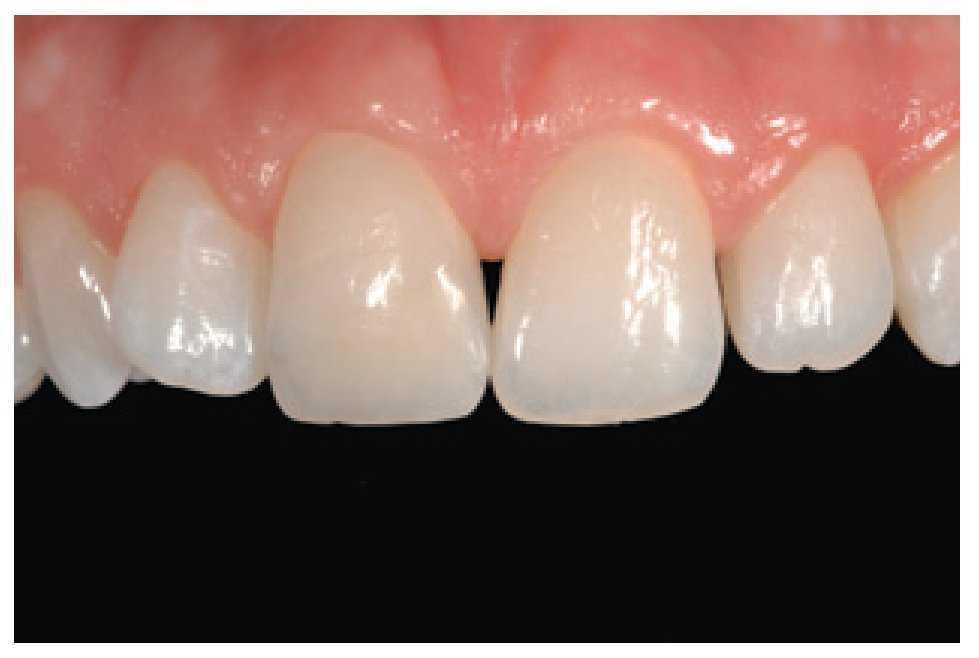

Figura 17 Paciente de 8 años de edad, con fractura traumática de los dientes 11 y 21.

Figura 18a y b Para conseguir una restauración estéticamente atractiva es importante controlar de forma concienzuda las capas de dentina y esmalte.

Figura 19 El caso, en una revisión después de un año.